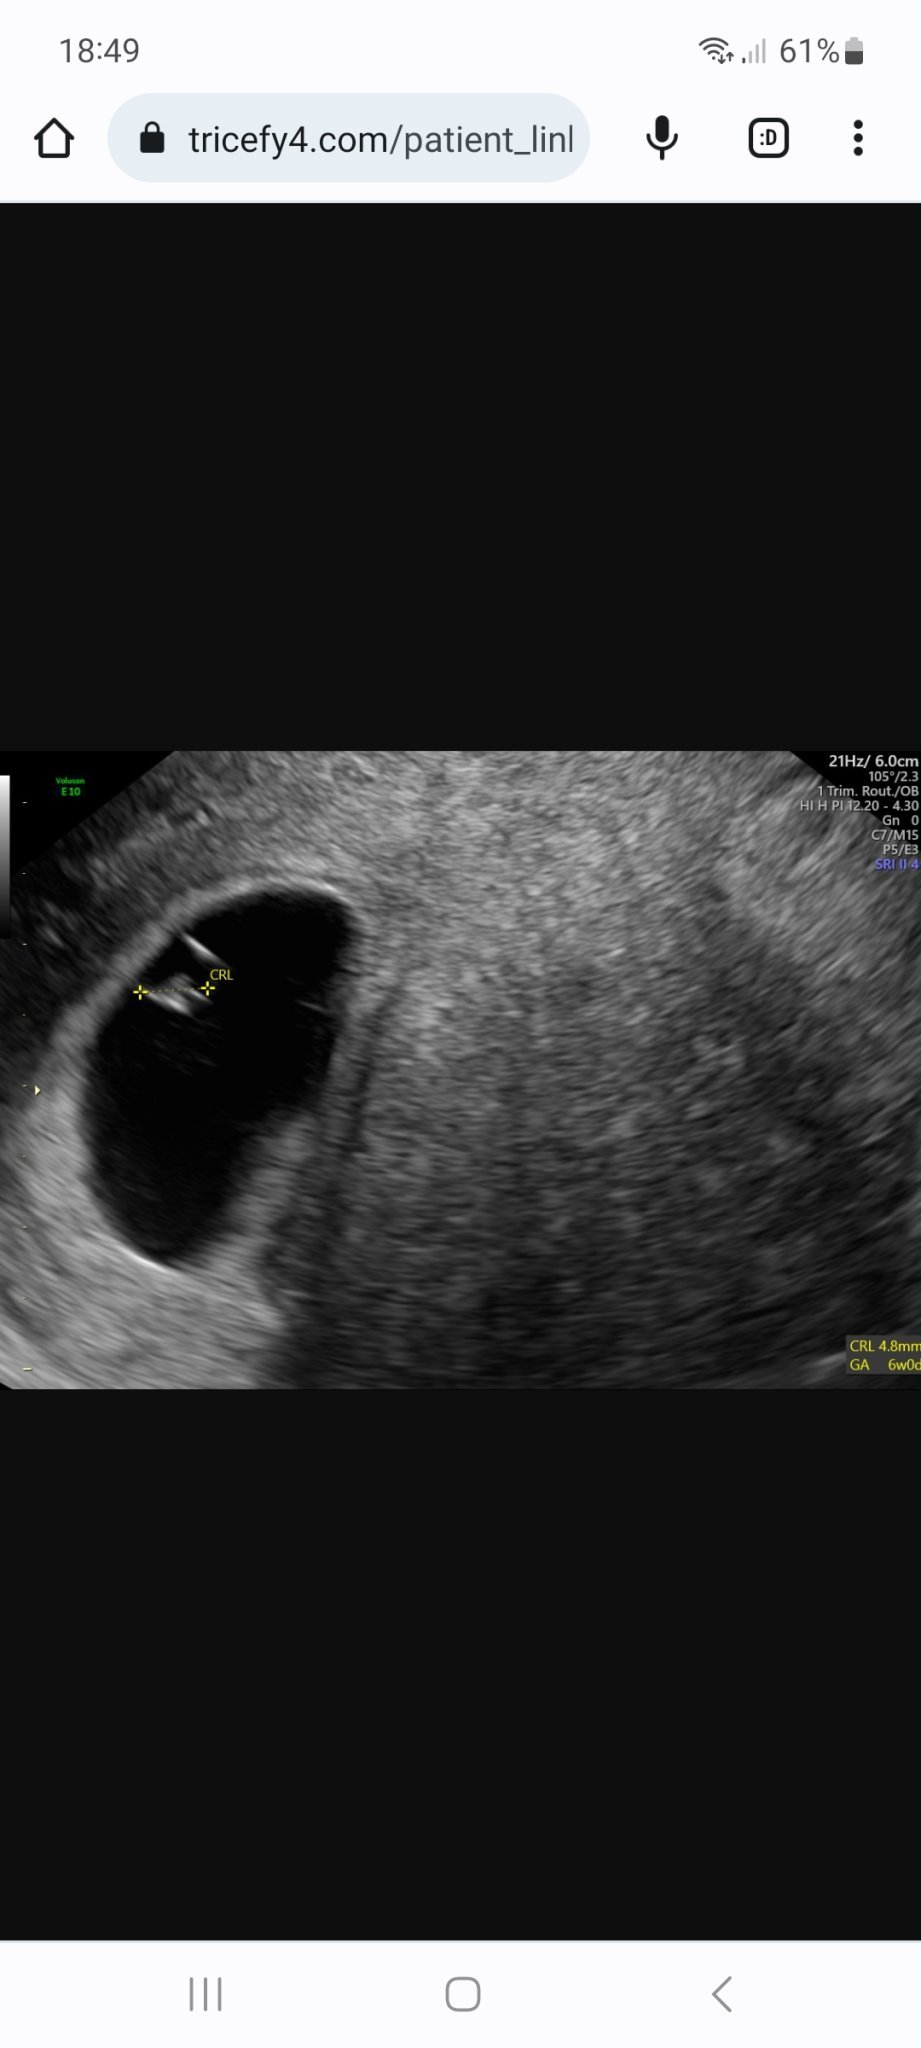

Здравейте , аз съм нова тук.  Бих искала да ми кажете мнението си за последните ми снимки - 9г.с и два дни - лекарят каза , че ембриона е спрял да се развива след 6та седмица. Каза да спра прогестерона и да чакам до 2-3 дни да получа спонтанен аборт.  Вие какво мислите .

Също така последната снимка, която ще кача е от предходния скан и не разбирам защо CRL е по голям -4.8мм , а снимката е от по ранна дата 05.05.2023 ???

Съжалявам за този развой. Но наистина размерите са на 6 седмично бебе и няма как, при положение, че трябва да си в девета г.с. да изостава толкова много. Пише по-голяма стойност, защото в тези ранни седмици е доста трудно да хване доктора точно началото и края на ембриончето, а това е 1 мм разлика. Би могла да отидеш на второ мнение, но ехографската снимка изглежда добра и надали докторът е сбъркал